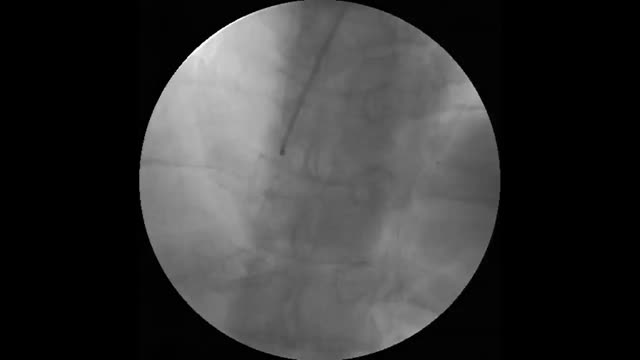

The following year, he developed NYHA class II to III congestive heart failure (HF), requiring uptitration of diuretics. The repeat echocardiogram showed moderate concentric left ventricular hypertrophy, with preserved ejection fraction but an abnormal global longitudinal strain and elevated filling pressures (Figure 3). He repeated the coronary angiography which excluded CAD progression. He underwent a 99mTc-DPD scintigraphy that revealed significant myocardial tracer uptake, diagnosing TTR amyloid infiltration (Figure 4). He was stabilized with medical therapy and kept under close follow-up, requiring antianginal therapy uptitration for exertional microvascular angina.